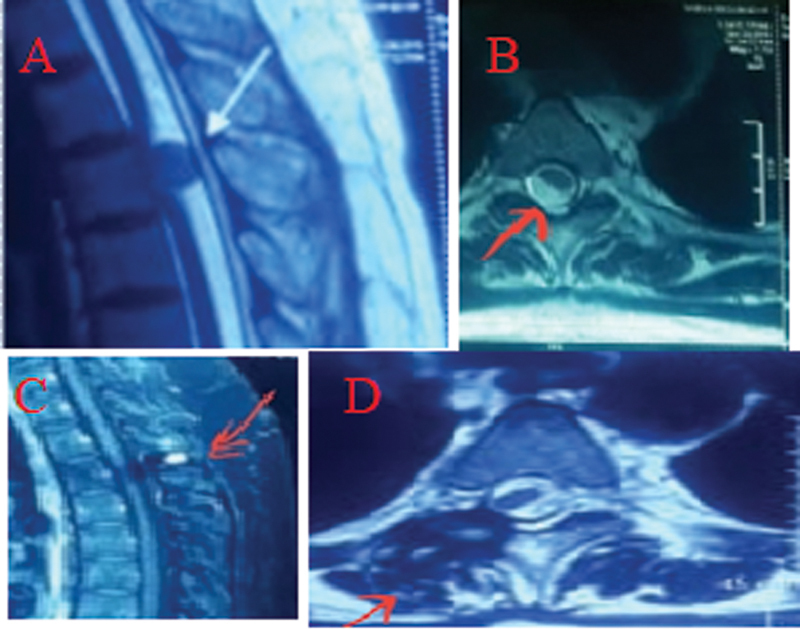

Materials and methods: A retrospective study was performed in 70 patients who were admitted between January 2017 and January 2024 with intradural spinal tumors and underwent excision with microscopic minimal invasive tubular retractor system. Patient's data including age, sex, clinical symptoms, and magnetic resonance imaging were collected. The extent of resection, surgical complications, estimated blood loss, estimated surgical time, and neurological outcomes were recorded. The neurological assessment was done by the modified McCormick grading scale pre- and postoperatively.

Results: Out of 70 patients, there were 38 (54.28%) males and 32 (45.71%) females, with a mean age of 45.16 (range: 8-79) years. The histology of these cases was meningioma (34.28%), schwannoma (51.42%), astrocytoma (2.85%), ependymoma (2.85%), and neurofibroma (8.57%). The average volume of tumors was 1.98 cm 3 , and gross total resection was achieved in 64 (91.53%) cases and subtotal resection was achieved in 6 (8.57%) cases. One patient had neurological deterioration, which was improved on follow-up after 6 months, and cerebrospinal fluid (CSF) leakage was noted in one case, which recovered after keeping lumbar drain for 5 days. No permanent neurological deficits were observed compared with their preoperative status, with improvement noted in visual analog scale and modified McCormick grade in all cases in the long-term follow-up evaluation (6-24 months).